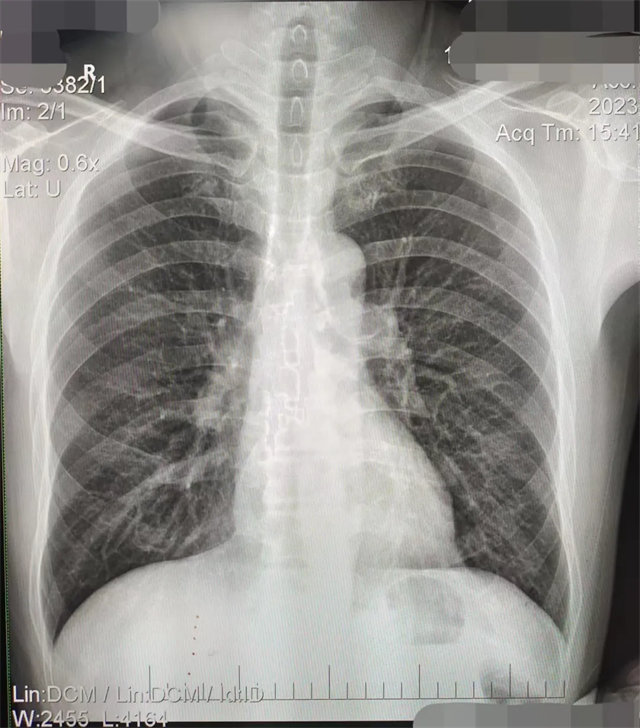

缺陷:雙側(cè)胸鎖關(guān)節(jié)不對稱,且有手機(jī)顯影。

解決:去除手機(jī)后,使患者左側(cè)緊貼成像件曝光。